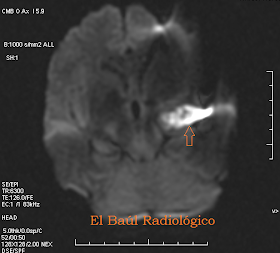

Mujer de 29 años.

FIGURA 5-A) Imagen FSE-T1. Lesión hipointensa, de contorno irregular, en el ángulo pontocerebeloso derecho. Contenido heterógeneo. Contorno y contenido son dos datos que orientan hacia el diagnóstico de epidermoide.

FIGURA 5-B) Imagen FLAIR-T2. Lesión heterogénea, bien delimitada (Flecha).

FIGURA 5-C) Imagen FSE-T2. Imagen hiperintensa de contornos bien delimitados. Produce una impronta muy acentuada sobre el pedúnculo cerebeloso medio derecho que pocos tumores pueden hacer.

FIGURA 5-D) Imagen FSE-DP.

FIGURA 5-E) Imagen SE-DWI. La lesión brilla en las imágenes potenciadas en Difusión Isotrópica.